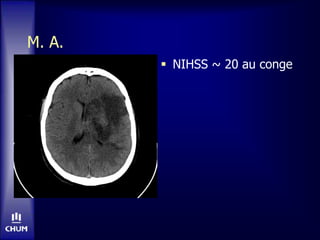

M. A.: unautre exemple...  Homme de 50 ans, droitier • Aucuns antecedents  AVC ACM gauche • NIHSS 9 (aphasie)  CT: pas de changements precoces  tPA-IV

M. A.  24hres post-tPA • Deterioration subite • NIHSS 23

M. A.  NIHSS~ 20 au conge

M. A.

 NIHSS ~ 20 au conge